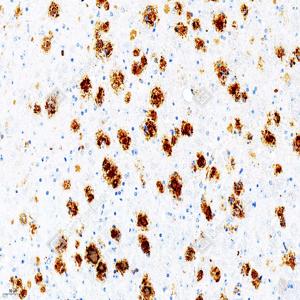

IHC检测beta Amyloid 1-42蛋白(货号 GB115755). 样品: 阿尔茨海默病FAD4T小鼠脑模型, 4%多聚甲醛 (货号G1101) 固定12-24小时. 抗原修复: 柠檬酸抗原修复液(干粉, pH 6.0) (G1201), 98℃, 20分钟. —抗: 1: 600稀释, 4℃ 孵育过夜. 二抗: S-vision免疫组化多聚二抗(山羊抗兔),即用型 (货号G1302), 室温孵育20分钟. |